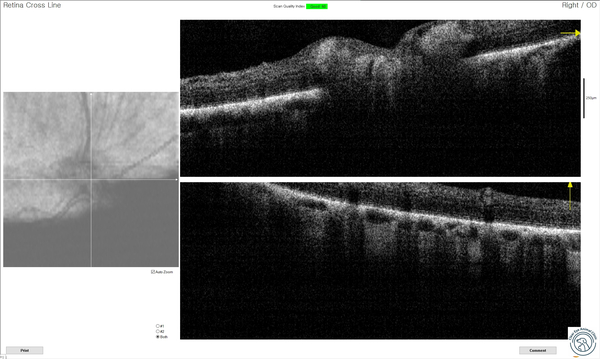

또한 OCT를 통해 시신경 상태도 확인합니다.